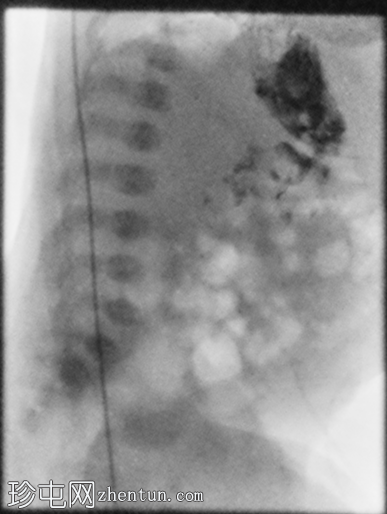

X线片

正位

胃部初始显影,并立即反流至食管裂孔疝。在其近端可见管径正常的远端食管。十二指肠降部和横部显影较弱,左上腹可见数段管径较小/部分减压的近端小肠显影。